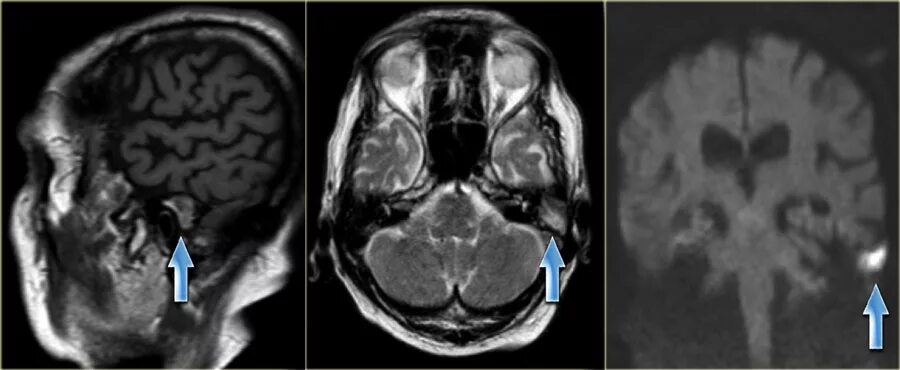

Мрт височных костей в режиме dwi